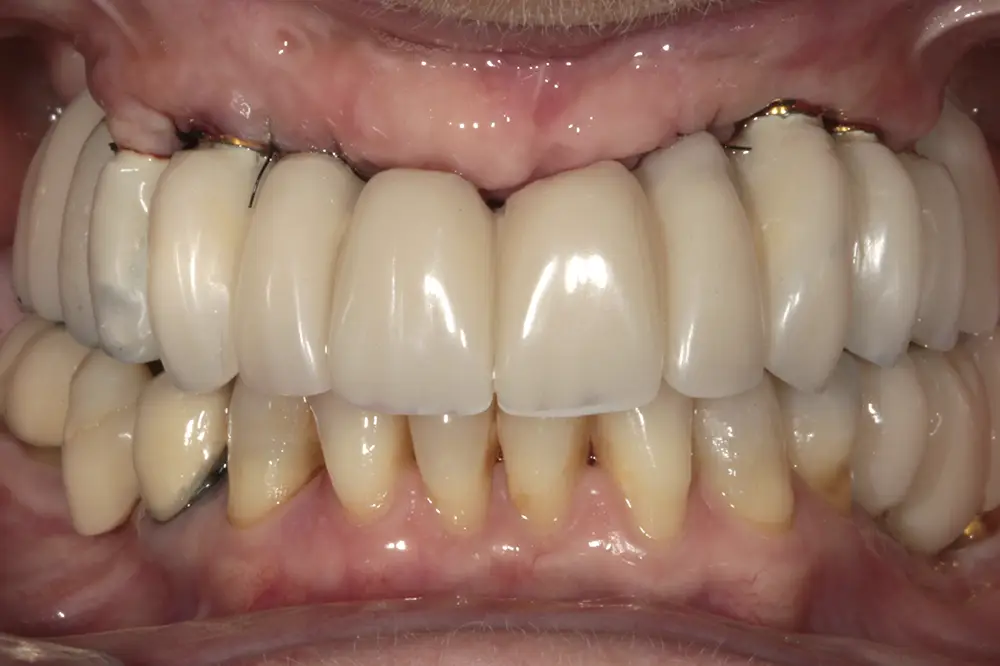

Para los sectores posteriores, se fabricaron estructuras mediante fresado CAD/CAM del mismo modo que la barra anteriormente descrita, con la diferencia de que sobre ellas se colocó un recubrimiento de cerámica (figs. 47-49). La paciente continúa en seguimiento, sin evidenciarse pérdidas óseas significativas en ninguno de los implantes estrechos y cortos que conforman la restauración de todo el maxilar superior tras tres años de carga de la prótesis definitiva (y hasta 4,5 de la carga de los implantes de la fase inicial de carga inmediata) (fig. 50).

Figs. 47 y 48. Prótesis terminadas, colocadas en la paciente.